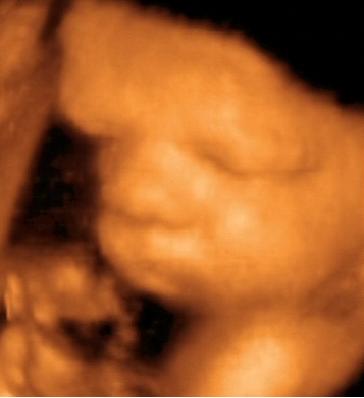

A lényeg. Lányunk lesz. Bár számomra ez nem volt egyértelmű a kép alapján...talán nektek az lesz. Már most kész óriás, 2703 g. Gyönyörű babó, bár most nem voltunk olyan szerencsések, mint a múltkor és folymatosan eltakarta magát. Nagyon fájt a szívem amikor láttam, hogy mennyire össze van "hajtogatva" szegénykém. a bal lába a homlokánál van :(. No de ez van. Remélem azért nem annyira rossz neki.

Küldöm a képeket is.